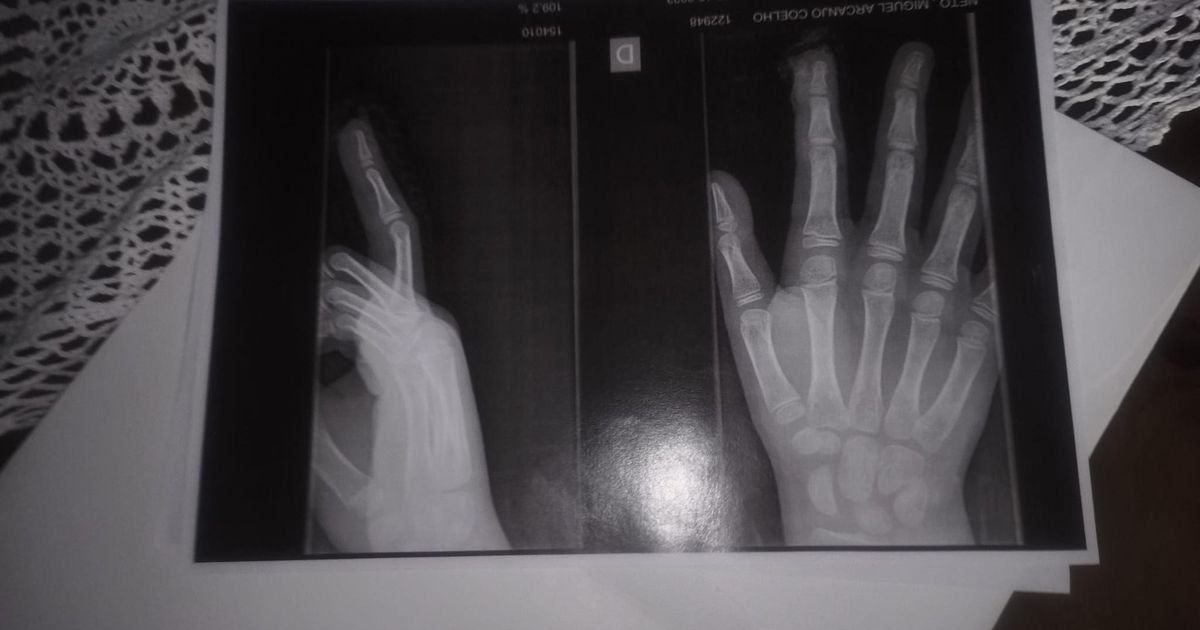

Imagem BBC Brasil

Foto mostra raio-x tirado por Miguel após incidente na escola Crédito: Arquivo pessoal

Michelly também foi chamada a escola depois que Miguel machucou os dedos da mão. Segundo o relato da criança, os colegas tentaram prendê-lo no banheiro e acabaram prendendo sua mão na porta.

"No centro de saúde, o médico falou: 'Mãe, foi por pouco'. Foi por pouco porque pegou no ossinho dele, mas não quebrou", conta a brasileira que vive deixou Natal, no Rio Grande no Norte, para viver em Portugal em 2022.